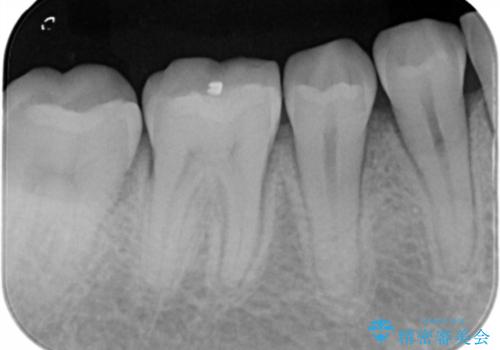

- 右下奥歯の虫歯治療を希望された患者様です。

保険の材料が劣化し、直下で虫歯の存在が確認出来ました。

セラミックを希望されたので形態・切削量を考慮し、セラミックインレーでの治療を計画しました。

虫歯が広く進行していましたが神経には到達していなかったので、予定通りセラミックインレーでの治療を行いました。